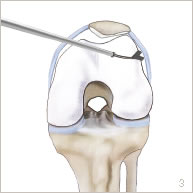

Elle est réalisée sous arthroscopie, c’est à dire sans ouvrir l’articulation. Deux petites incisions de 5 mm chacune sont réalisées en avant du genou. Une petite caméra est introduite par l’une d’entre elles pour visualiser l’articulation. Des petits instruments sont introduits par l’autre incision pour sectionner l’aileron (figures 3 et 7).

La rotule va alors se recentrer et l’aileron externe ainsi sectionné va par la suite cicatriser de façon moins tendue, ce qui permet l’engagement de la rotule dans la trochlée sans contraintes excessives (figure 4).